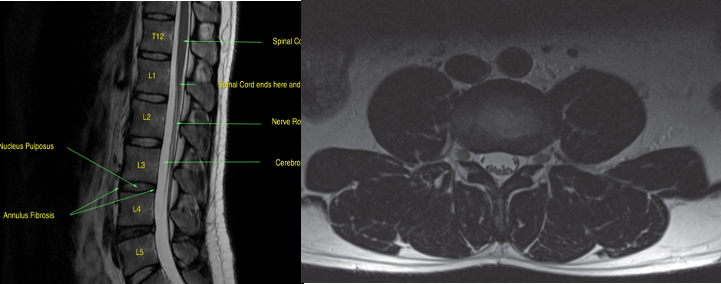

Axial T2-weighted scan through the L3/L4 disc space.

At this level, the L3 nerve roots are in the exit foramina and the L4 nerve roots have moved to the edge of the dural sac in the lateral recesses prior to exiting the spinal canal at the level below.